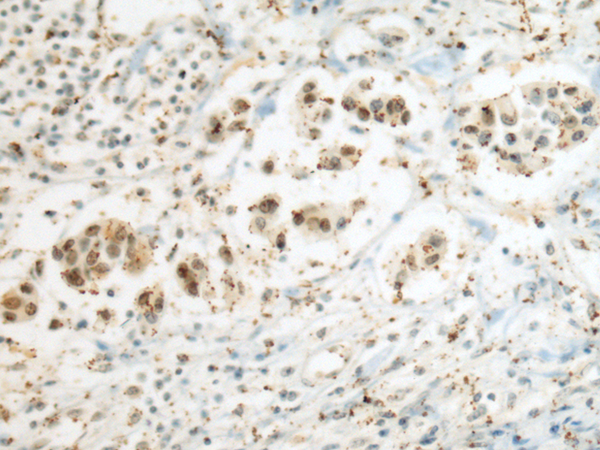

IHC positive control: |

Human breast cancer |

IHC Recommend dilution: |

50-200 |